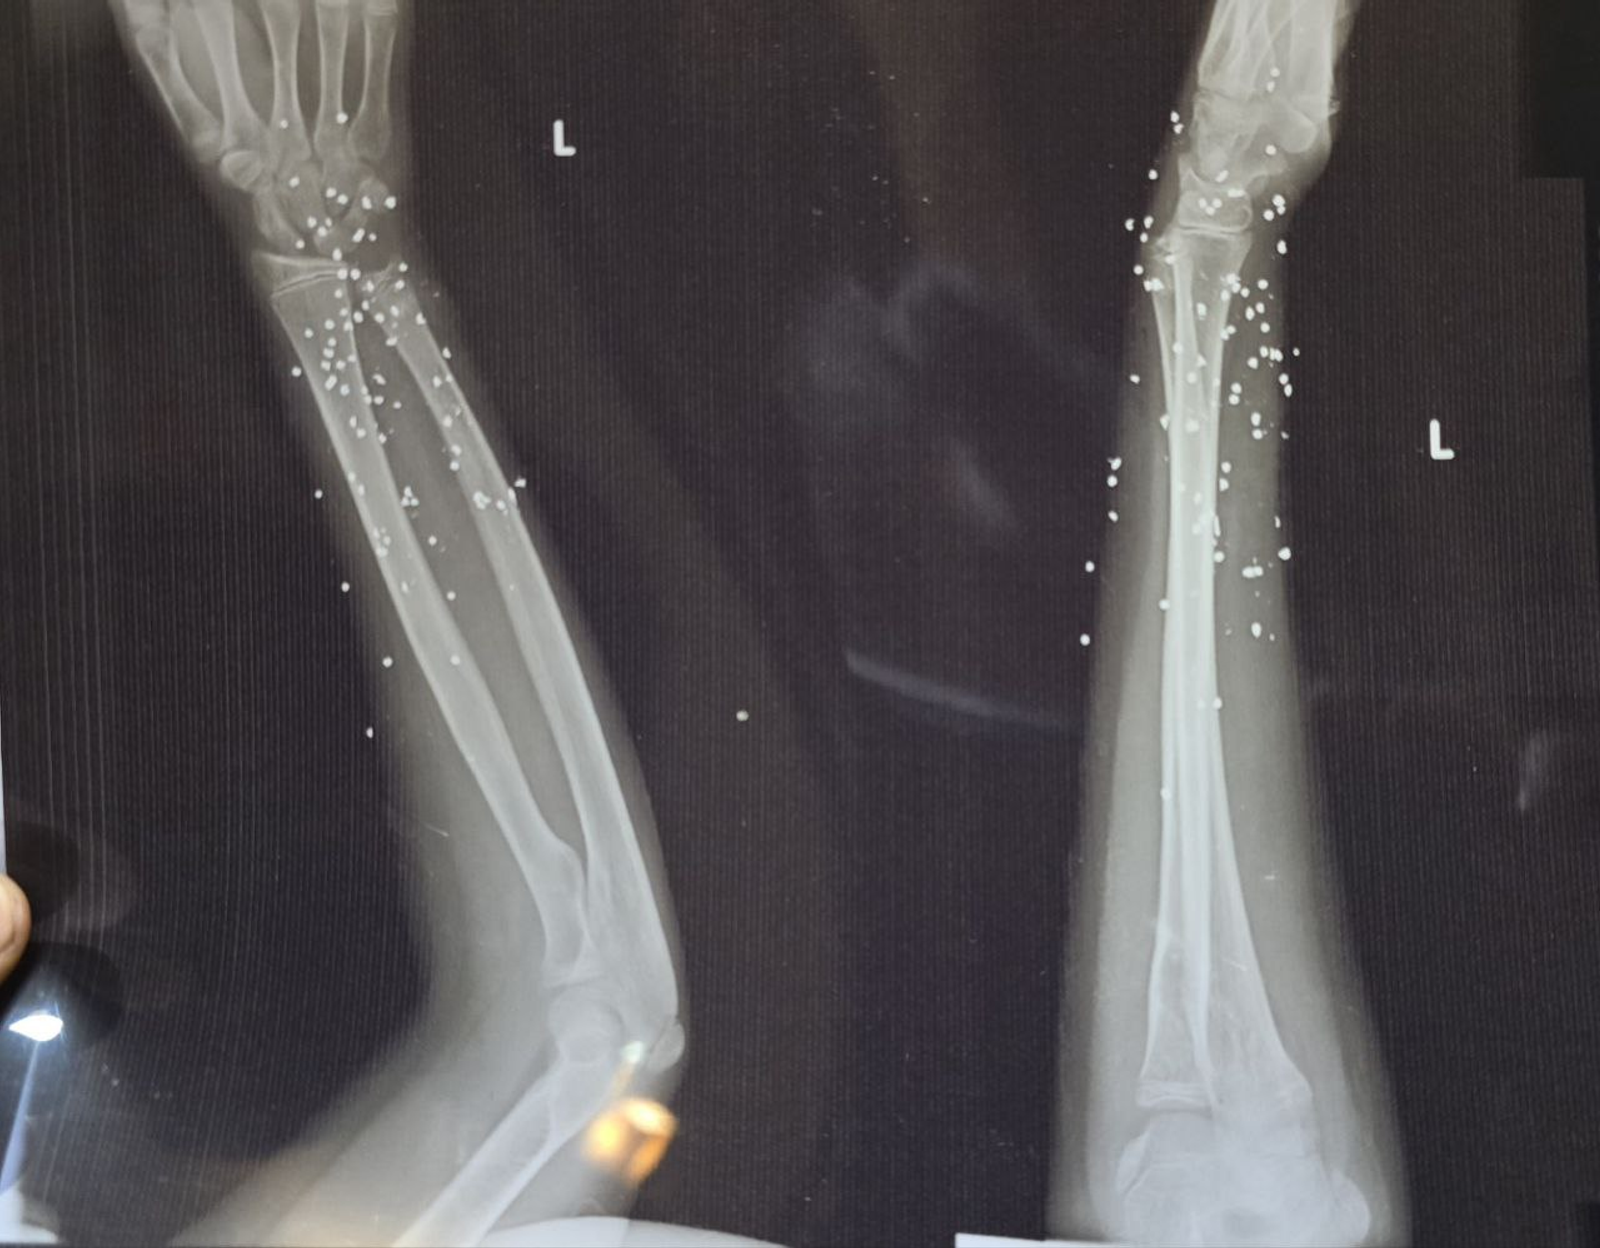

به گزارش روزنامه گاردین، بررسی ده‌ها تصویر پزشکی ثبت‌شده در جریان سرکوب اعتراضات در ایران نشان می‌دهد معترضان با ساچمه‌های فلزی و گلوله‌های کالیبر بالا هدف قرار گرفته‌اند. تصاویری که به گفته کارشناسان، از شدت جراحات و الگوی اصابت به نواحی حیاتی بدن حکایت دارند.

تصویر او یکی از بیش از ۷۵ مجموعه تصویر پزشکی شامل رادیولوژی و سی‌تی‌اسکن است که از یک بیمارستان در یکی از شهرهای بزرگ ایران به دست آمده و در اختیار گاردین قرار گرفته است. تصاویری که در طول یک شب و هم‌زمان با سرکوب اعتراضات دی‌ماه ثبت شده‌اند.

تصاویر، روایتی از شدت خشونت علیه معترضان و رهگذران ارائه می‌دهند.

ساچمه‌هایی که می‌توانند مرگبار باشند

ایران از معدود کشورهایی است که نیروهای امنیتی آن از ساچمه فلزی علیه شهروندان و برای سرکوب معترضان استفاده می‌کنند. هرچند هر ساچمه به‌اندازه گلوله جنگی قدرت تخریب ندارد، اما تعداد زیاد آن‌ها می‌تواند آسیب‌هایی بسیار شدید ایجاد کند.

گاردین در گزارش خود تاکید کرد که در برخی تصاویر، تنها یک یا دو ساچمه در جمجمه دیده می‌شود که پس از عبور از چشم در حفره آن متوقف شده‌اند.

در موارد دیگر، صدها ساچمه در بدن پراکنده شده و بافت نرم را تخریب کرده‌اند.

در پرونده «علی»، بیش از ۱۷۴ ساچمه در قفسه سینه راست دیده می‌شود. تراکمی که نشان می‌دهد شلیک از فاصله بسیار نزدیک انجام شده است. ریه راست او آسیب شدید دیده و تجمع خون و هوا در اطراف آن مشاهده می‌شود.

کارشناسان پزشکی گفته‌اند حتی با مداخله فوری، خطر مرگ در چنین شرایطی بالاست.

گلوله‌های تمام‌فلزی

در ۹ بیمار، گلوله‌های کالیبر بالا همچنان در بدن باقی مانده و در تصاویر دیده می‌شوند.

در موارد دیگر، مسیر شکستگی استخوان و قطعات فلزی باقی‌مانده نشان می‌دهد احتمالا اصابت گلوله‌های پرسرعت، عامل جراحت بوده‌اند.

کارشناسان این مهمات را از نوع «تمام‌فلزی» معرفی کرده‌اند؛ گلوله‌هایی که معمولا با سلاح‌هایی مانند ای‌کی-۴۷ (AK-47) شلیک می‌شوند و شکل خود را حفظ می‌کنند.

یکی از کارشناسان به گاردین گفته است: «این‌ها سلاح‌هایی با هدف کشندگی هستند.»